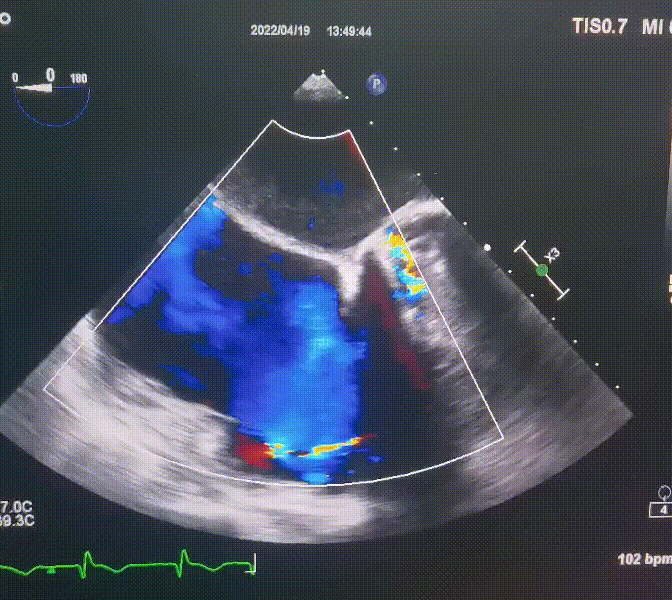

術前超聲提示:

1.右心、左房明顯增大;

2.二尖瓣人工機械瓣功能正常,無瓣周漏;

3.三尖瓣環巨大擴張,收縮期瓣葉對合不攏,收縮期三尖瓣房側見大量反流信號,反流面積15-20cm²,TRVmax:240cm/s,跨瓣壓差:23 mmHg。

圖1.術前超聲